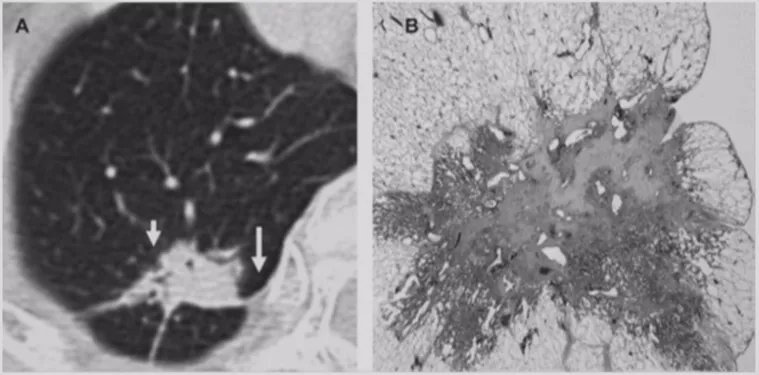

如上图所示,一般来说这么小的病灶我们可能忽略,但这个病人做了手术,不仅是恶性肿瘤,而且是微浸润腺癌。实际上我们在临床上要把这么多结节甄别出来,是十分具有挑战性的。病人一旦患有肺结节,也面临着很多问题,比如焦虑、心理压力等。所以我们既不能过度诊断,但也不能延误诊断。